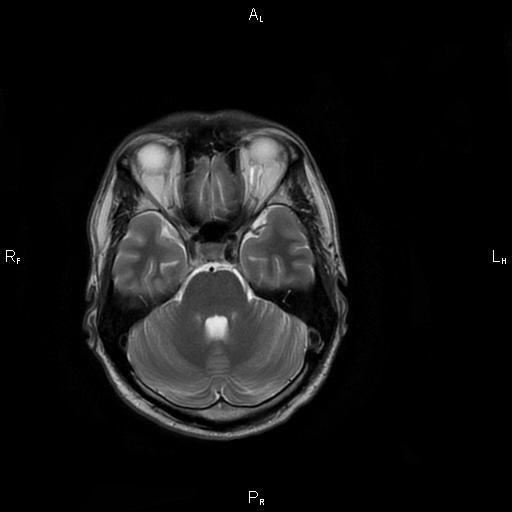

8. Рис. 3а

Тема

Тип Материалы исследования

Посмотреть (11KB)

Метаданные ▾

9. Рис. 3б

10. Рис. 3в

Посмотреть (13KB)